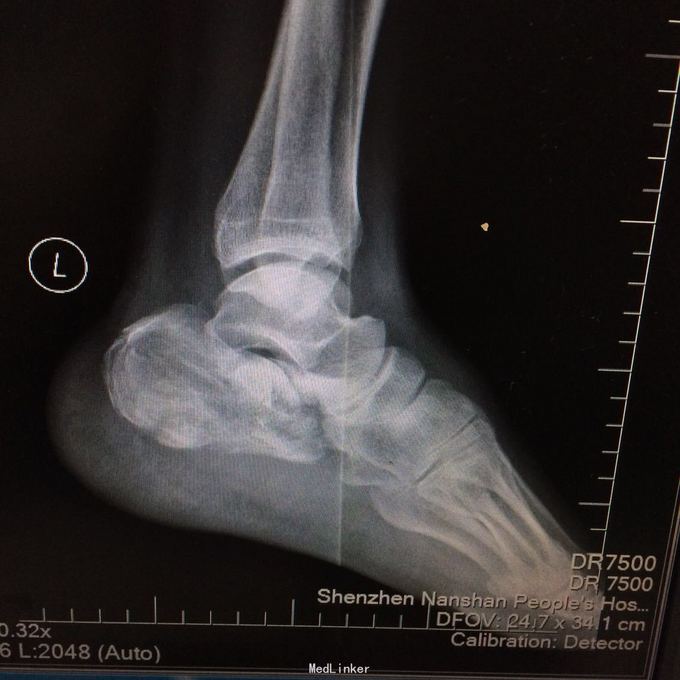

患者某某,男,49岁,因“高处坠落致全身多处疼痛、肿胀、流血2小时 1、男性壮年患者。 2、缘患者于2小时前因高处坠落致左肘、左手、右手、头面部、左胸,左足等多处受伤,即觉左肘部疼痛、活动困难、流血;左手、头面部伤口疼痛、流血;右手、左胸,左足部等处疼痛、肿胀。由家属、同事送往我院就诊,经行X线检查示:左肱骨远端粉碎性骨折,左肘关节半脱位;左手第4、5掌骨远端骨折;右手第1远节指骨基底部、第3、4远节指骨骨折,第5中节、远节指骨骨折;左跟骨粉碎性骨折。CT示:鼻中隔骨折;右侧第3--7肋骨折。急诊科予清创包扎止血,为作进一步诊治而收入院。患者受伤以来,患者精神好,无呼吸困难,无恶心、呕吐,无头晕,无面色苍白,无双下肢麻木、无力,无大小便失禁。 3、查体:T36.8 ℃ P 76次/分 R20 次/分 BP104/67mmHg。神清合作、应答切题、全身皮肤粘膜无黄染、浅表淋巴结无肿大。头颅五官无畸形,左眉弓处见一长约2cm伤口,活动性出血,巩膜无黄染,双侧瞳孔等大等圆,直径 3 mm,对光反射灵敏。鼻梁有一长约3cm纵行伤,深及皮下,伴有活动性出血;下唇部见一1*1cm组织缺损,伴活动性出血.颈软,无抵抗,气管居中,甲状腺无肿大,胸廓无畸形,右侧胸部局部压痛明显,胸廓挤压征阳性;心前区无隆起,双肺叩诊清音,呼吸音清,无干湿性罗音。心率76次/分,律齐有力,各瓣膜区无病理性杂音。腹平,腹肌软,全腹压痛、无反跳痛,肝脾肋下未及,双肾区无叩痛,无移动性浊音,肠鸣音存在,4-6次/分。脊柱、骨盆无压痛,四肢检查详见专科情况,其余肢体检查正常。双下肢生理反射存在,病理性反射未引出。

4、专科情况:左肘部中度肿胀,呈短缩、成角畸形,局部皮肤活动性出血,局部压痛明显,纵向叩击痛,左肘部可扪及骨擦感,有反常活动,左肘部活动障碍。左肩峰至肱骨外上髁上臂长度较右侧短缩1厘米,左手掌尺侧轻度肿胀,无畸形,局部皮肤正常,局部压痛明显,可扪及骨擦感,无反常活动,左手指活动正常。左侧手指肌力Ⅳ级,有牵拉痛,左上肢手指末梢血运良好,感觉略差。右手拇指、环指及尾指局部皮肤组织撕脱,渗血明显;右手中指末端损毁,局部缺失。右手手指肌力Ⅳ级末梢血运良好。左足跟部肿胀明显,局部皮肤正常,局部压痛明显,纵向叩击痛,左足跟部可扪及骨擦感,左足趾肌力Ⅳ级,无牵拉痛,左足趾末梢血运及感觉良好。 5、辅助检查:本院2015年11月14日X线检查示:左肱骨远端粉碎性骨折,左肘关节半脱位;左手第4、5掌骨远端骨折;右手第1远节指骨基底部、第3、4远节指骨骨折,第5中节、远节指骨骨折;左跟骨粉碎性骨折。CT示:鼻中隔骨折;右侧第3--7肋骨折;左下肺挫伤。

1、左肱骨远端粉碎性开放性骨折;2、左肘关节半脱位;3、左手第4、5掌骨远端骨折;4、右手第1、3、4远节指骨骨折;5、右手第5中节、远节指骨骨折;6、鼻部软组织挫裂伤;鼻中隔骨折;7、右侧第3--7肋骨折;8、左跟骨粉碎性骨折;9、左眉弓软质挫裂伤;10、左肺挫伤;11、脑震荡。 1.完善三大常规、PT四项、生化等各项常规检查; 2.完善CT检查,予抗破伤风、抗感染、镇痛、止血等对症支持治疗; 3.请口腔、耳鼻喉、眼科等相关科室会诊; 4.请示上级医师,指导下步治疗。 手术时间:2015年11月15日 术后诊断:左肱骨远端开放性粉碎性骨折 麻醉方式:全身麻醉 手术名称:左肱骨远端开放性粉碎性骨折清创缝合外固定架固定术 手术时间:2015年12月25日 术后诊断:左肱骨远端粉碎性骨折 麻醉方式:臂丛麻醉 手术名称:左肱骨远端粉碎性骨折切开复位内固定术 。 手术时间:2015-12-3 术后诊断:左跟骨粉碎性骨折;左肱骨远端粉碎性开放性骨折;左肘关节半脱位;左手第4、5掌骨远端骨折;右手第1、3、4远节指骨骨折;右手第5中节、远节指骨骨折;右足拇趾撕脱骨折并趾间关节脱位;鼻部软组织挫裂伤;鼻中隔骨折;右侧第3--7肋骨折;左眉弓挫裂伤;左肺挫伤;脑震荡。 麻醉方式:腰硬联合 手术名称:左跟骨粉碎性骨折切开复位钛板内固定术